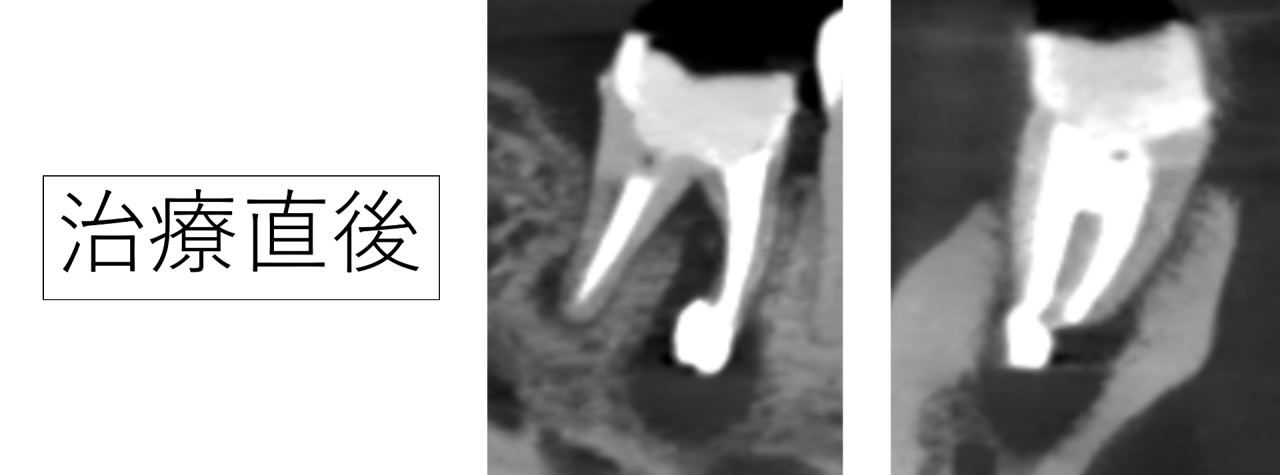

治療後の経過と骨の再生

治療から1年後、溶けていた骨の部分に新しい骨の再生がはっきりと確認され、歯の周囲がしっかりと支えられる状態になっていました。MTAセメントによる特殊根管治療が上手くいったようです。

・治療後、骨の再生がレントゲンで確認された